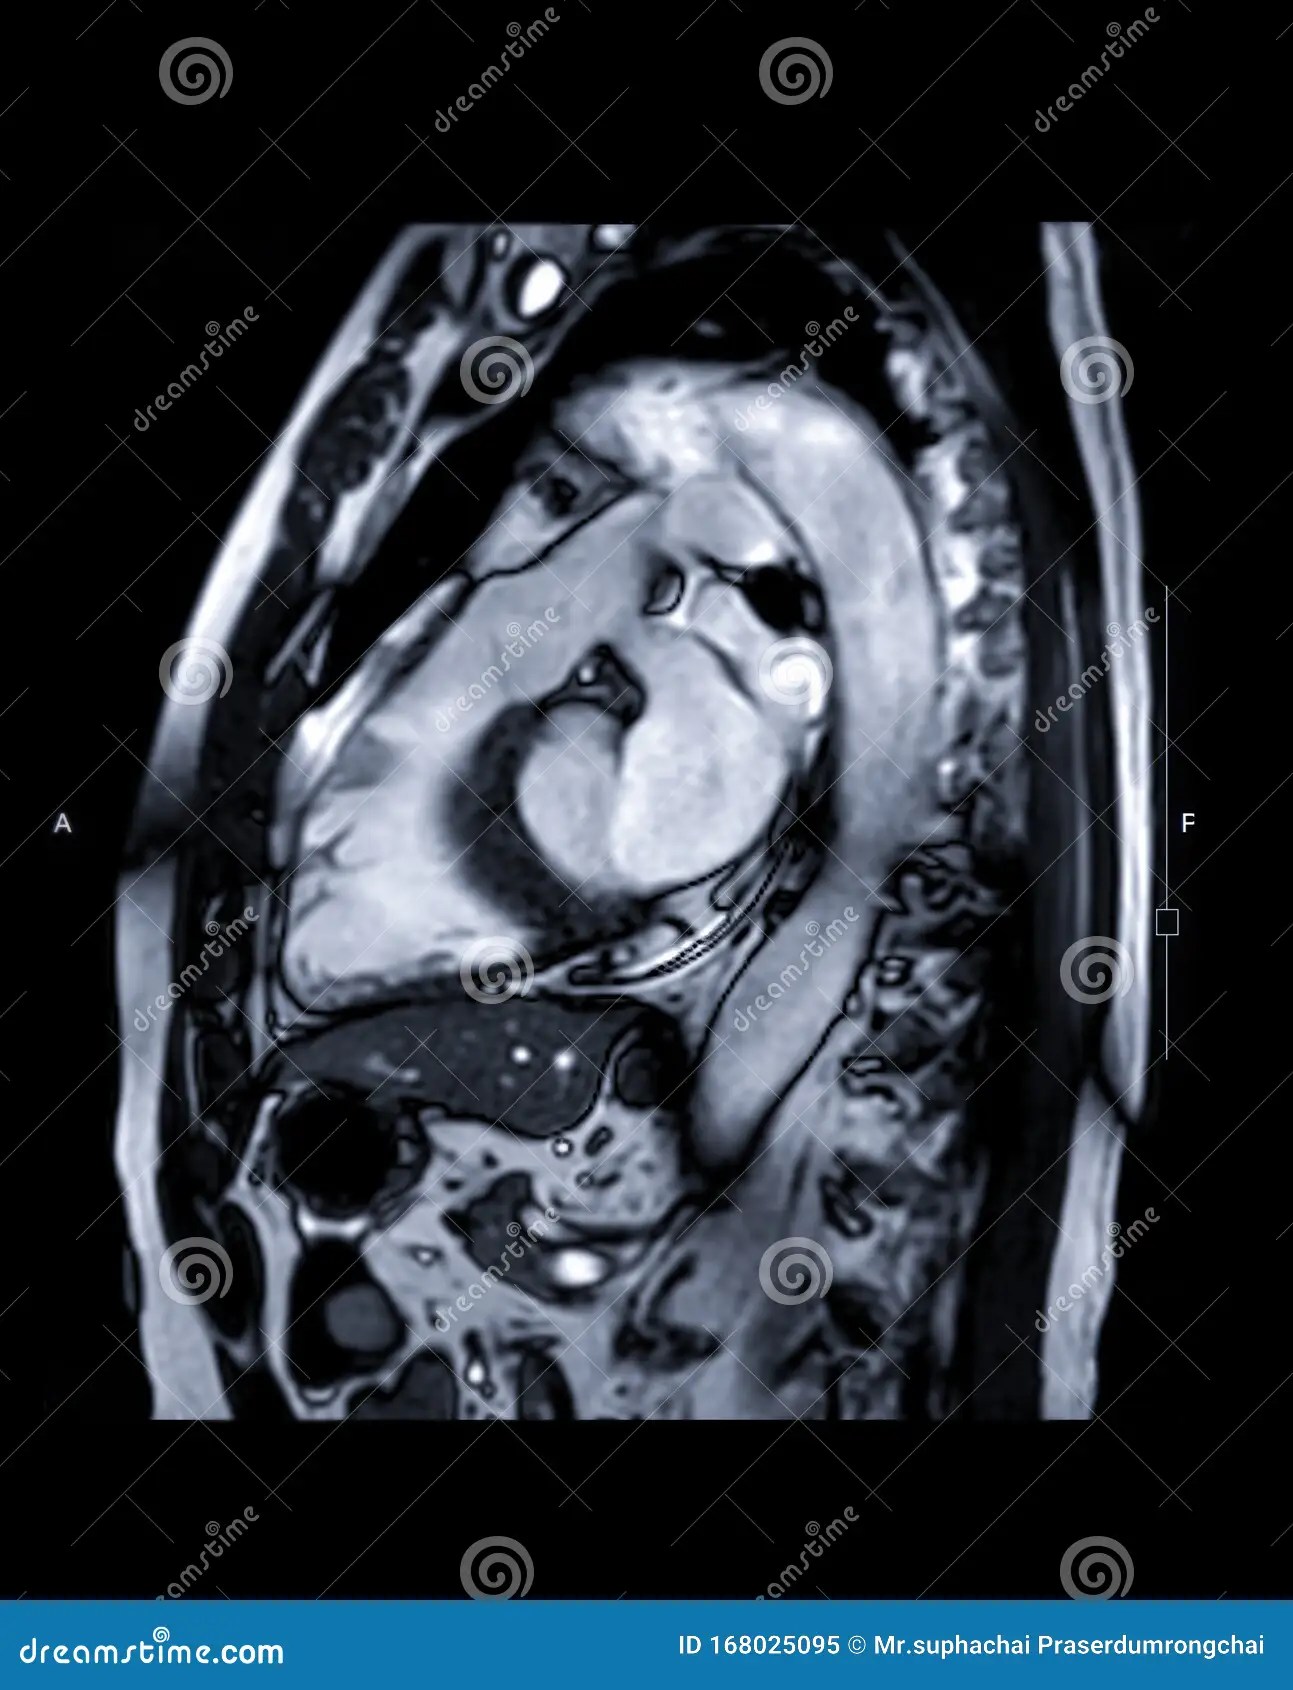

Cardiac magnetic resonance imaging (CMR) has emerged as a powerful non-invasive imaging modality in the diagnosis and management of a wide range of cardiovascular diseases. With its ability to provide high-resolution, three-dimensional images of the heart, CMR offers unique insights into cardiac structure, function, and tissue characterization. This article aims to provide a comprehensive overview of the role of CMR in the diagnosis of various cardiac conditions, highlighting its strengths, limitations, and clinical applications.

Cardiac magnetic resonance imaging (CMR) is a versatile and powerful imaging modality that plays a crucial role in the diagnosis and management of a wide range of cardiovascular diseases. With its ability to provide high-resolution, three-dimensional images of the heart, CMR offers unique insights into cardiac structure, function, and tissue characterization. While CMR has some limitations, its advantages make it an invaluable tool for clinicians in the evaluation of cardiac conditions. As the field of CMR continues to evolve, it is expected to play an even greater role in the future of cardiovascular medicine.